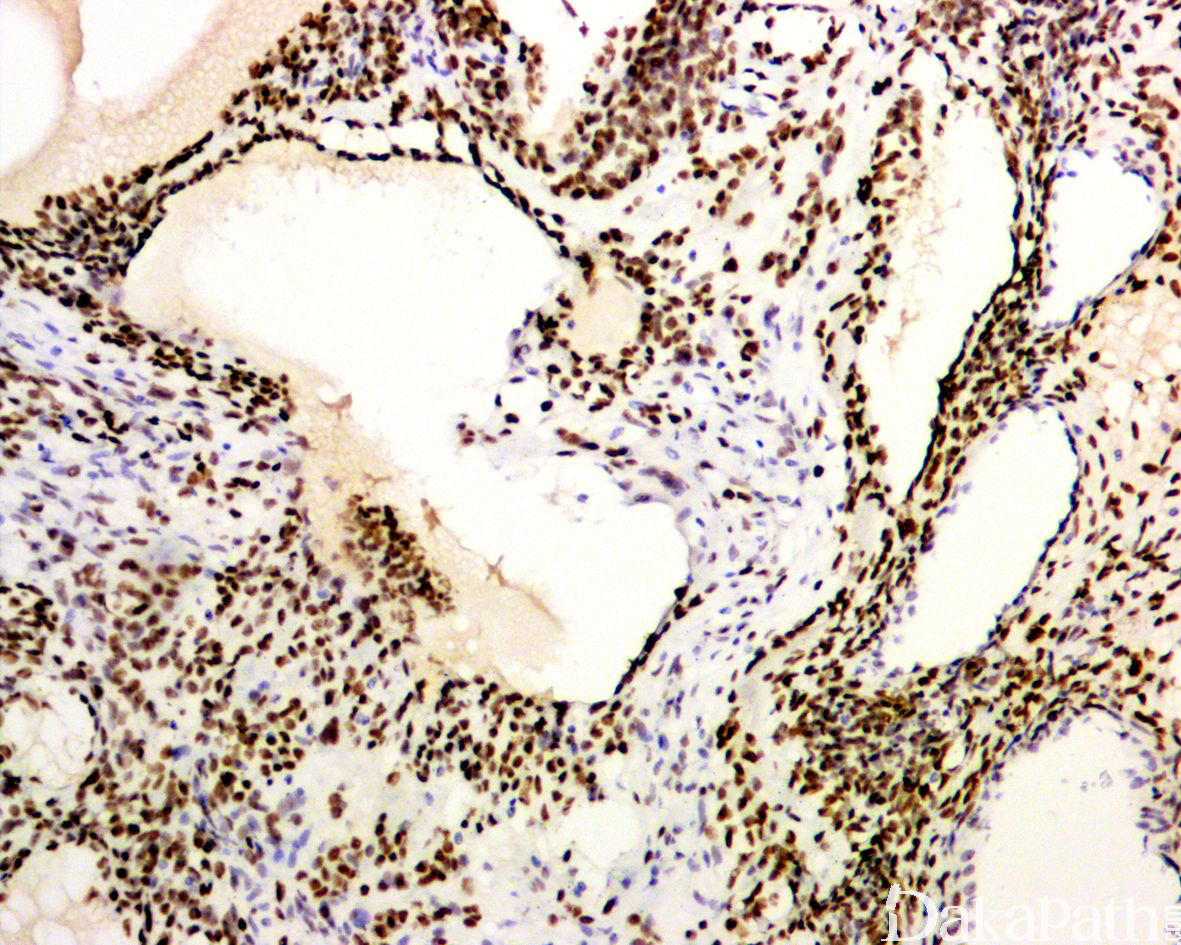

- 免疫组织化学染色:上皮性标志物抗体:CK、EMA、CK7. CK8. CK14. CK18. CK19 阳性;间叶性标志物抗体:VIM 阳性;不同程度表达 CD99. S100. SMA、calponin、h-caldesmon、MSA;多不表达 CD34. desmin;

免疫组织化学染色:

上皮性标志物抗体:CK、EMA、CK7. CK8. CK14. CK18. CK19 阳性;间叶性标志物抗体:VIM 阳性;不同程度表达 TFE1. bcl2. CD99. S100. SMA、calponin、h-caldesmon、MSA;多不表达 CD34. desmin, 极少数可显示 H3K27me3 表达缺失和 INI-1 的马赛克样表达缺失;